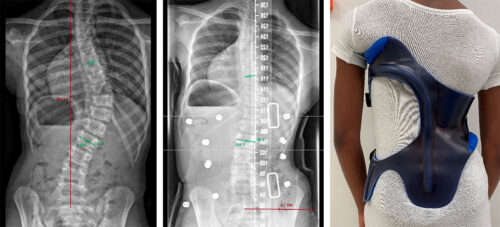

يعاني العديد من الأطفال والمراهقين من اعوجاج العمود الفقري (Scoliosis)، وهو انحناء جانبي غير طبيعي للعمود الفقري قد يؤثر على المظهر العام للجسم ووضعية القفص الصدري. أحد أهم طرق العلاج غير الجراحية في الحالات النشطة هو الحزام الطبي، الذي يهدف إلى تثبيت الانحناء ومنع تفاقمه أثناء نمو الطفل. ومع ذلك، يطرح الأهل كثير من الأسئلة: ما خطورة تأخير استخدام الحزام؟ وماذا يحدث إذا لم يبدأ العلاج في الوقت المناسب؟ هذا المقال يجيب على كل هذه الأسئلة بطريقة مبسطة وسهلة الفهم.

الحزام لا يصحح الانحناء بشكل كامل، لكنه يقلل من الحاجة للتدخل الجراحي في المستقبل إذا تم استخدامه مبكرًا وباستمرار.

تُظهر الأدلة أن الحزام خيار فعّال وموثوق في علاج اعوجاج العمود الفقري، خاصة في حالات الانحراف القطني والصدري السفلي. كما تُشير النتائج إلى أن الحزام لا يُستخدم فقط لتقويم الانحناء، بل يساهم أيضًا في تحسين التوازن الجسدي والمظهر العام.

امنح طفلك فرصة أفضل لمستقبل صحي مع حزام PioBrace المتطور من مركز الرواد. يتميز هذا الحزام بتقنيات تقويم متقدمة تضمن نسبة تصحيح عالية لاعوجاج العمود الفقري، مع اعتماد فريق طبي متخصص يراقب التقدم بشكل مستمر لضمان عدم تفاقم الانحناء مستقبلاً. اختروا مركز الرواد، حيث تلتقي الخبرة الطبية بأحدث الابتكارات، لنوفر لطفلكم علاجًا مخصصًا وآمنًا يعيد التوازن لجسمه بثقة واحترافية. صحتهم أمانة ونحن هنا لنحافظ عليها.

لماذا يجب عليكم اختيار حزام PioBrace؟

- راحة استثنائية: يتميز حزام PioBrace بتصميمه الذي يوفر أقصى درجات الراحة للأطفال طوال فترة العلاج.

- فعالية مثبتة علميًا: يساعد الحزام في إيقاف تقدم الاعوجاج وتقليل الحاجة إلى التدخل الجراحي.